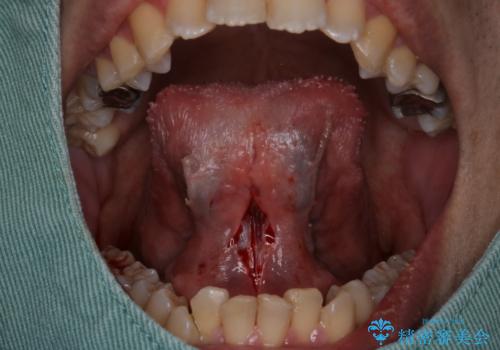

『即日手術』滑舌が悪いのを改善したい!

- 滑舌が気になるため舌小帯の切除を希望し来院されました。

ベロが動かせるようになってすごく喜ばれておりました。